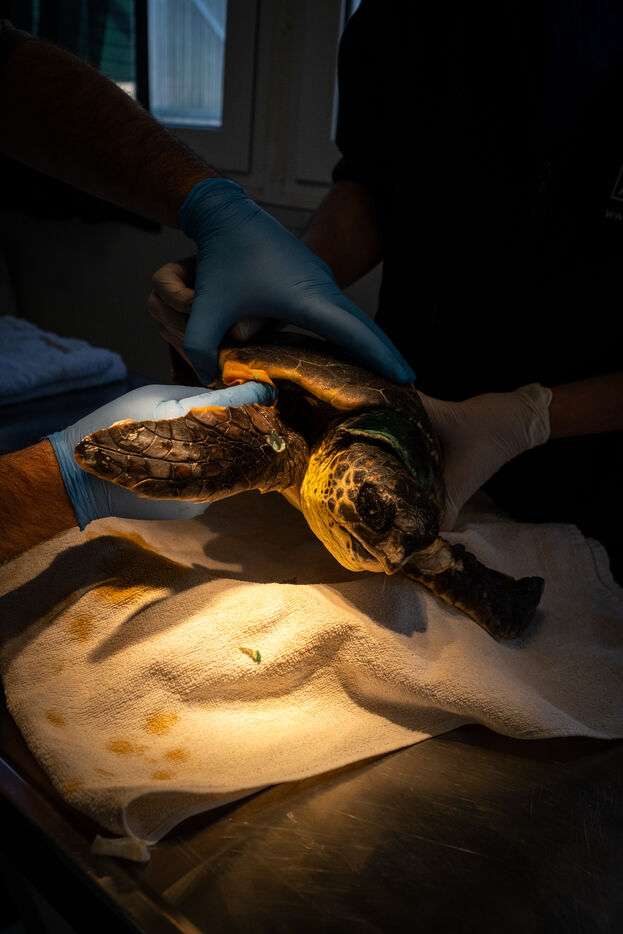

Les vétérinaires veillent aussi de près sur les tortues. Ils passent effectuer des relevés ou encore installer une perfusion. Parfois, ils emmènent une tortue dans le bloc opératoire pour des interventions plus complexe. Les tortues doivent parfois être amputés d'une ou plusieurs nageoires. « Malgré cela, elles peuvent souvent retourner dans la nature, ce sont des animaux puissants. » nous dit la biologiste. Des poids sont souvent fixés sur les carapaces des tortues. Les blessures à la tête causant des troubles neurologiques, l'installation de plaques de métal lestées leur aident à retrouver l'équilibre et à nager de nouveau.

Léa, une toute petite tortue Caouanne de 3 ans, a été trouvée sur la côte à proximité du centre par Alex, volontaire franco-canadien, qui a plongé pour aller la sauver. Elle présente des blessures sérieuses au cou et à la nageoire dues à un emmêlement dans un filet de pêche. « De plus, après avoir effectué une radiographie, nous nous sommes aperçus qu'elle a également ingéré un hameçon de pêche. » explique Alex. Eirini détaille son traitement ; « piqûres d'antibiotiques, de vitamines ainsi que le nettoyage des plaies. Malheureusement, sa nageoire est gravement endommagée, elle va devoir être amputée mais avant cela nous devons lui enlever l'hameçon qui est dans son estomac quand elle aura repris des forces. En attendant, elle a une perfusion de fluides car elle ne se nourrit pas. On ne peut pas savoir le temps dont elle va avoir besoin pour se rétablir, sûrement 4 ou 5 mois. Nous ne sommes pas sûrs qu'elle s'en sortira. »

The vets also keep a close eye on the turtles. They drop in to take readings or set up perfusions. Sometimes they take a tortoise into the operating theatre for more complex operations. Turtles sometimes have to have one or more of their flippers removed. "Despite this, they are often able to return to the wild, as they are powerful animals," says the biologist. Weights are often attached to turtle shells. As head injuries cause neurological disorders, weighted metal plates help them to regain their balance and swim again.

Lea, a tiny 3-year-old loggerhead sea turtle, was found on the coast near the centre by French-Canadian volunteer Alex, who dived in to rescue her. She had serious injuries to her neck and flipper caused by entanglement in a fishing net. "What's more, after carrying out an X-ray, we realised that she had also ingested a fishing hook," explains Alex. Eirini details her treatment: "injections of antibiotics, vitamins and cleaning of the wounds. Unfortunately, her flipper is badly damaged and she will have to be amputated, but before that we have to remove the hook from her stomach once she has regained her strength. In the meantime, she is on a fluid drip as she is not feeding. We don't know how long she'll need to recover, probably 4 or 5 months. We're not sure she'll pull through."